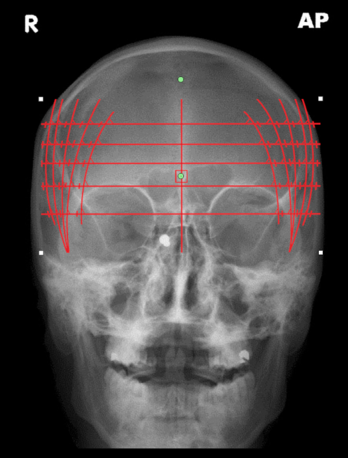

9.5.11. Frontal Cephalic Line (FCL) Template

The frontal cephalic line (FCL) template is used to find the frontal cephalic line. Follow the instructions below to use this tool:

1.      Select the ‘Frontal Cephalic line’ from the advanced section of the chiropractic toolbox

2.      Click on the image and the template will appear.

3.      To move the template: click on the template and drag it to the desired location.

4.      To resize the template: click on the any of the white points located on the outer corners and move it to adjust the dimensions.

5.      To rotate the template: click on the green point and a wheel will appear for you to click and rotate the template.

An example of this template is shown below: